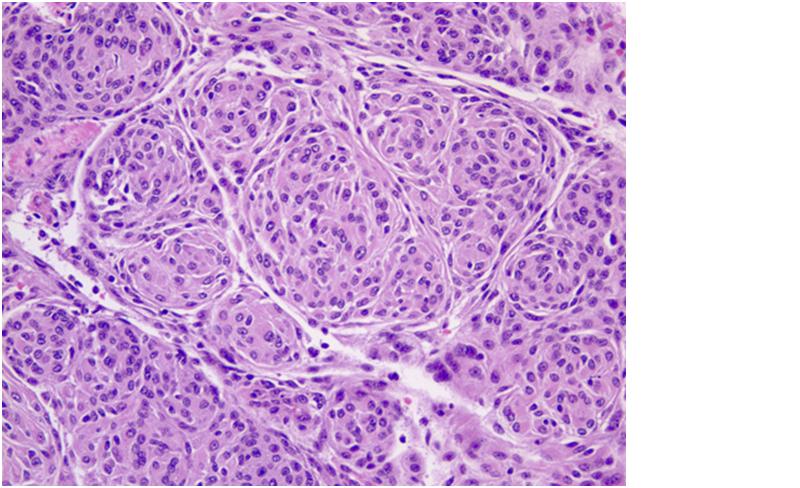

FIGURE 1: Sphenoid wing meningioma (H&E, 20x). Image depicts whorls of meningothelial cells composed of bland epithelioid type cells with eosinophilic cytoplasm arranged in a syncitium. The nuclei are ovoid with vacuoles and pseudo-inclusions.